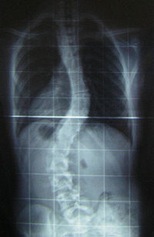

The image shown here is the scout film of cadaver 33448. Notice how the spine has a slight C-shaped curve involving the lower thoracic and lumbar vertebrae. The curve is convex toward the patient's left.

This is the scout film and CT scan of cadaver 33486, which shows a case of thoracic levoscoliosis (left convexity) and lumbar dextroscoliosis (right convexity). Look first at the anterior-posterior scout film to appreciate the curvature and make reference of where the major curves are, then look at the CT scan and watch the spine curve first to the left then the right as you scan from thoracic to lumbar vertebrae.